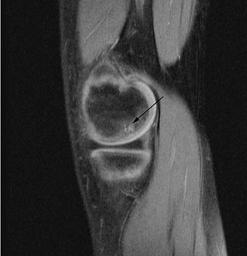

MAKE A MEME View Large Image OCD WalterReed MRI-Sagital-T1.jpeg en Sagittal and coronal T1 and T2 images demonstrate linear low T1 high T2 signal at the articular surfaces of the lateral aspects of the medial femoral condyles bilaterally corresponding to the ...

Keywords: OCD WalterReed MRI-Sagital-T1.jpeg en Sagittal and coronal T1 and T2 images demonstrate linear low T1 high T2 signal at the articular surfaces of the lateral aspects of the medial femoral condyles bilaterally corresponding to the radiographs confirming the presence of bilateral osteochondritis dissecans with diffuse increase in T2 signal at the medial femoral condyles indicating marrow edema From the case of a 9-year-old buy with bilateral knee pain Uniformed Services University Obtained from MedPix Database http //rad usuhs mil/medpix/medpix_image html imageid 14469 Pil Kang 2003-02-04 PD-USGov Magnetic resonance imaging of the knee MRI of osteochondritis dissecans